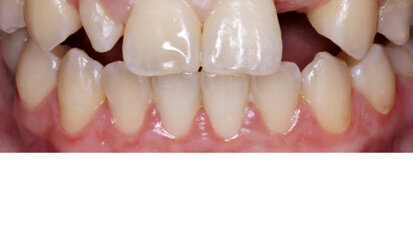

Nový úsměv za jeden den

Čt. 28. května 2020